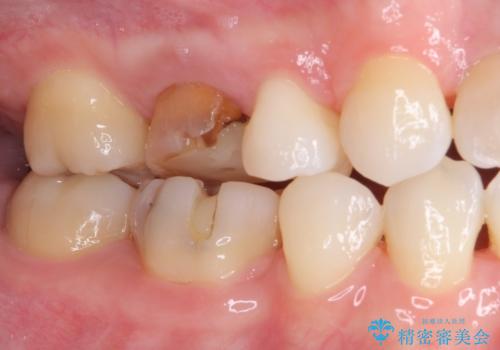

- 虫歯により神経を取り除いた前歯の変色が気になるとのことで来院された患者様です。

レントゲン写真より、歯根の炎症が認められなかったため、ファイバーコアによる土台築製後、オーダーメイドタイプのオールセラミッククラウンにて補綴することとしました。